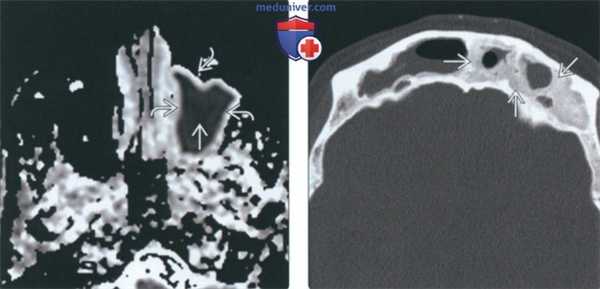

(Слева) При аксиальной КТ в костном окне у пациента с гранулематозом Вегенера определяются типичные для ХРС изменения верхнечелюаных пазух, пневматизация которых, а также полости носа снижена вследствие наличия мягкотканного компонента. Определяется также остеит стенок пазух.

(Справа) При корональной КТ в костном окне у ребенка с муковисцидозом определяется утолщение слизистой оболочки обеих верхнечелюстных пазух, визуализируются уровни жидкости, подтверждающие присоединение острого инфекционною процесса на фоне хроническою воспаления. Остеит у этого ребенка еще не развился в силу его возраста.

(Слева) На аксиальной КТ в костном окне у пациента с гранулематозом Вегенера определяются типичные признаки двухстороннего хронического гайморита. Нарушена пневматизация пазух и полости носа за счет мягких тканей. Определяются также выраженные признаки остеита стенок пазух.

(Справа) На корональной КТ в коаном окне у ребенка с муковисцидозом определяется утолщение слизиаой оболочки обеих верхнечелюаных пазух. Края утолщенной слизистой оболочки бугристые. Присутствуют уровни жидкости, свидетельствующие о наложении оарой инфекции на хроническое воспаление. Остеит у этого ребенка еще не возник в силу его возраста.